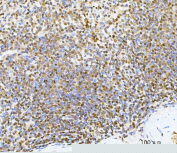

IHC analysis of c-Myc in human spleen tissue. Paraffin-embedded human spleen tissue was stained with c-Myc / MYC antibody following pH8 EDTA heat-mediated antigen retrieval. Nuclear immunoreactivity is observed in lymphoid cells, consistent with endogenous c-Myc expression. Scale bar: 100 um.